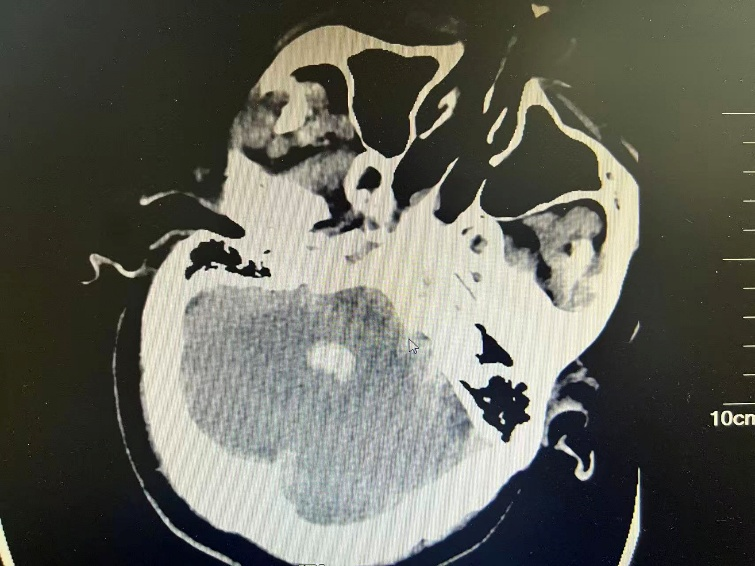

2025年12月8日晚9时许,我院针康二科护士在病区楼道发现护工赵某意识不清、呼之不应,并伴有呕吐。情况紧急,护士立即将其送至急诊科。经急诊颅脑CT检查,提示为“左侧丘脑出血破入脑室,双侧侧脑室及第四脑室血肿铸型”,病情危重,需立即手术干预。

图1

(配图说明:图1-2为术前颅脑CT,显示脑室系统血肿铸型;图3为术后复查CT,显示引流管位置良好;图4为手术团队术中操作场景。)